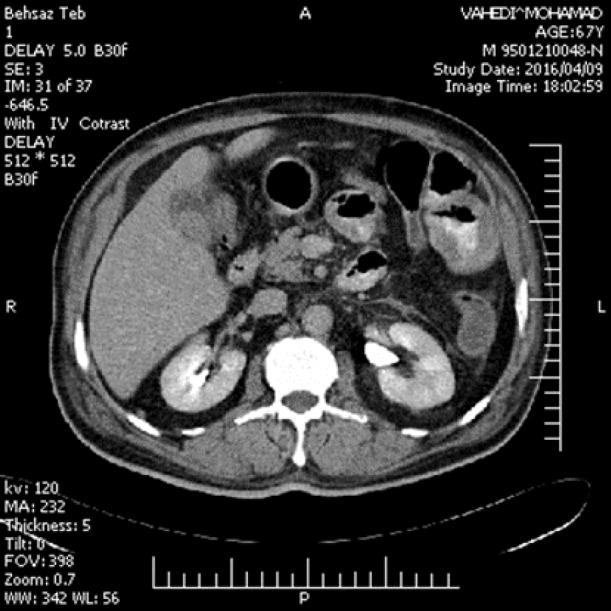

A 68-year-old man presented with a history of iron deficiency anemia. The upper gastrointestinal endoscopy showed a prominent papilla of duodenum along with an ulcerative lesion adjacent to second part of duodenum. Histopathologic evaluation showed a high-grade malignant neoplasm involving the bowel wall which was labeled for S100 protein and markers of melanocytic differentiation; Melan-A indicating the definitive diagnosis of malignant melanoma of the second portion of duodenal mucosa.

一名68岁男性,有缺铁性贫血病史。上消化道内镜检查显示十二指肠乳头突出,十二指肠第二部附近有溃疡性病变。组织病理学评估显示,累及肠壁的高级别恶性肿瘤标记为S100蛋白和黑素细胞分化标志物;Melan-A表明十二指肠黏膜第二部恶性黑色素瘤的明确诊断。